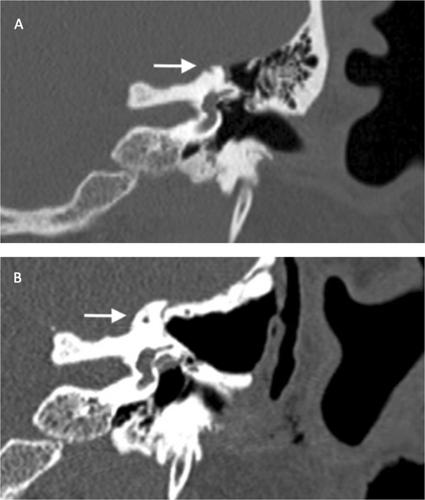

This retrospective case series was carried out at a tertiary referral center. All patients were ≥ 18-years-old diagnosed with SSCD between 2012 and 2022 and underwent a transmastoid approach implementing hydroxyapatite capping. Dehiscence location and size were assessed by reviewing preoperative CT temporal bone scans and correlated to the success rate of surgical repair. The failure rate (lack of symptom resolution and/or persistent dehiscence on postoperative imaging) and/or need for revision surgery were evaluated.

Twenty-two patients (25 ears) were included. Mean age was 50.8 years (SD = 9.9 years) with 50.0% female patients (n = 11). The predominant location of SSCD was determined as apical (76.0%, n = 19), followed by anterior limb (12.0%, n = 3) and posterior limb (12.0%, n = 3). Mean dehiscence size was 2.8 mm (SD = 1.4 mm). Median follow-up time after repair was 9.0 months (interquartile range: 2–36 months). Failure rate was 8.0% (n = 2). Both cases demonstrated persistent SSCD on postoperative imaging; one case had a residual apical dehiscence of 1.6 mm persistent at 4 months, and one had a posterior-apical dehiscence of 2.3 mm persistent at 8 months after surgery.